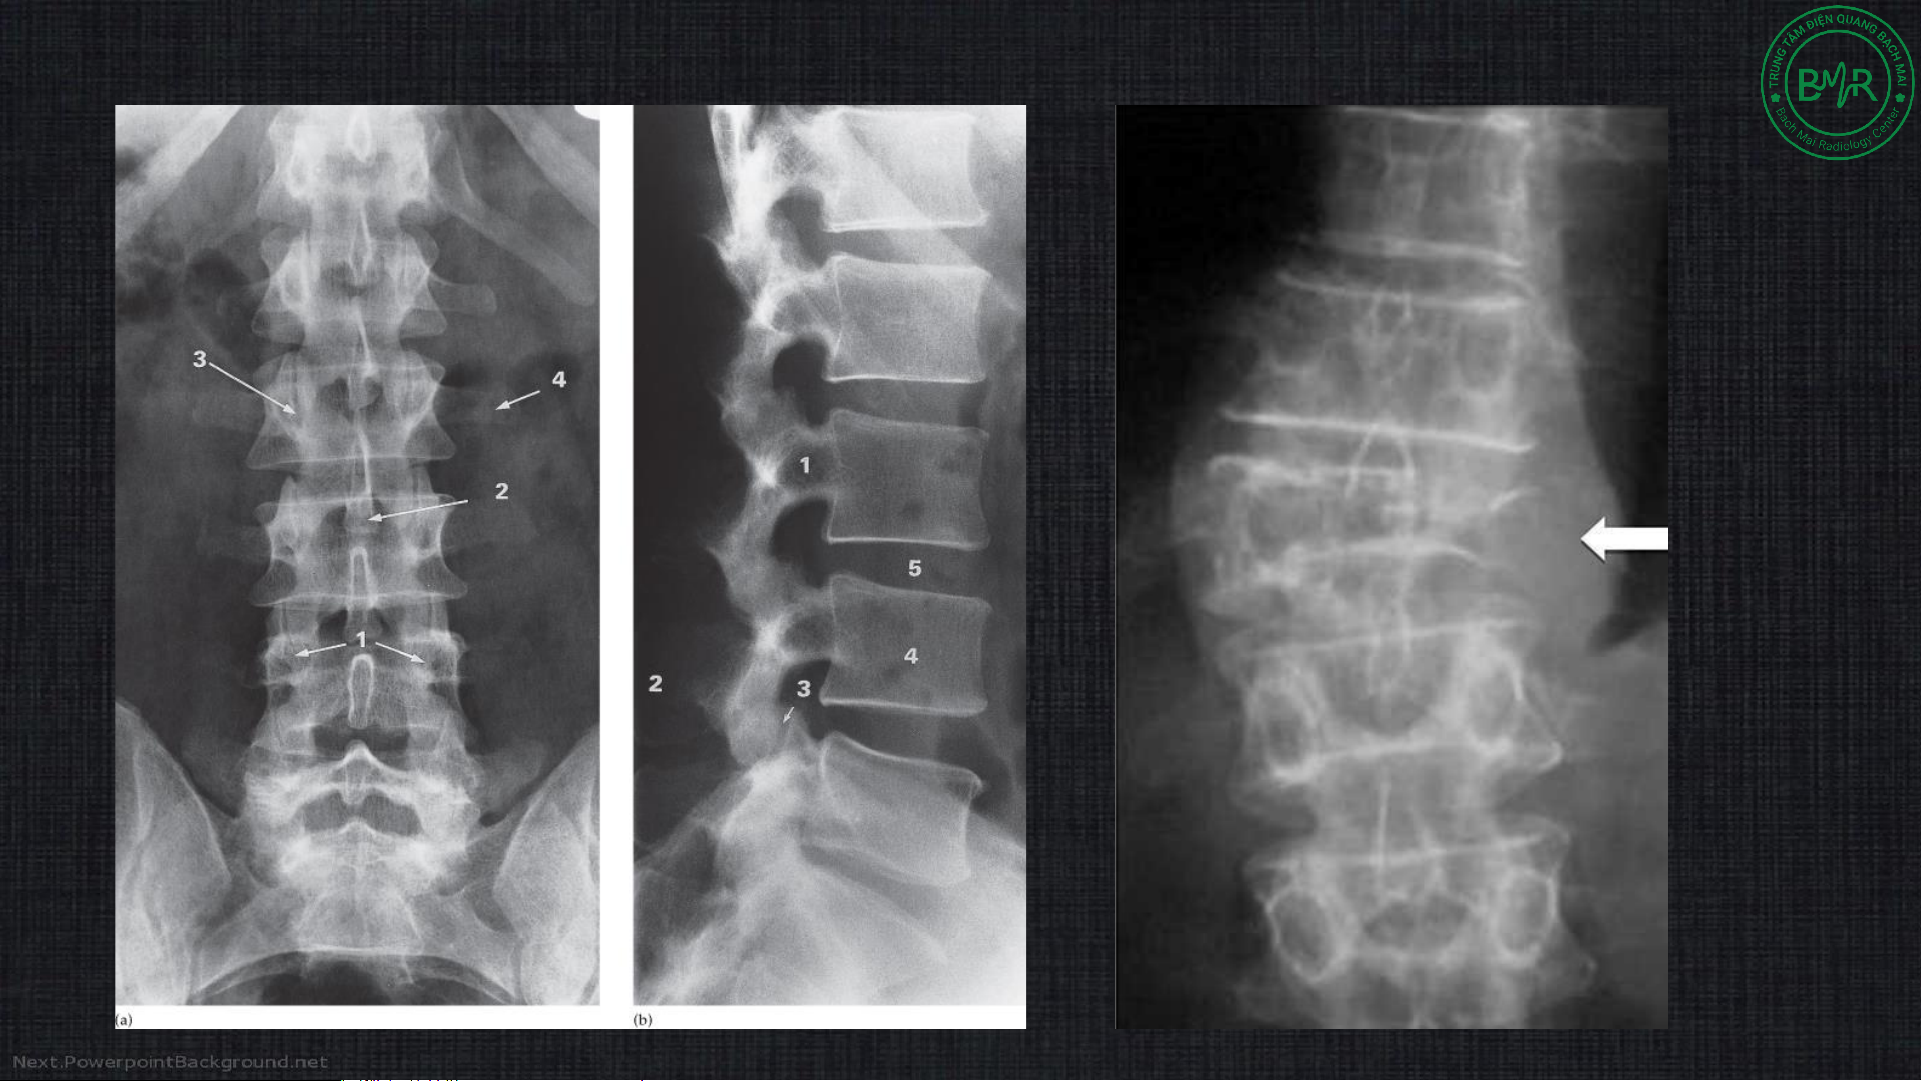

2. Các phương pháp thăm khám • Xquang

• Chụp tủy sống (myelography) • Cắt lớp vi tính • Cộng hưởng từ 2a. Xquang 2a. Xquang Ứng dụng • Xquang thường quy:

• Đánh giá chủ yếu cột sống

• Các bệnh lý thoái hóa, u, chấn thương (các đường cạnh sống), dị tật…